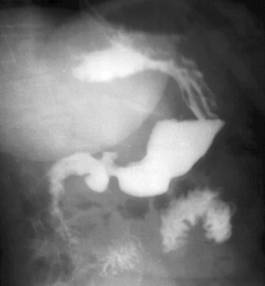

Image TOGD mono contrast

baryte un ulcere bulbaire sclerosante avec image de

niche arondie au milieure de la bulbe |

|

Ulcere bulbaire sclerosant

avec deformation en etoile du bulbe . Technique TOGD

a double de contrast |